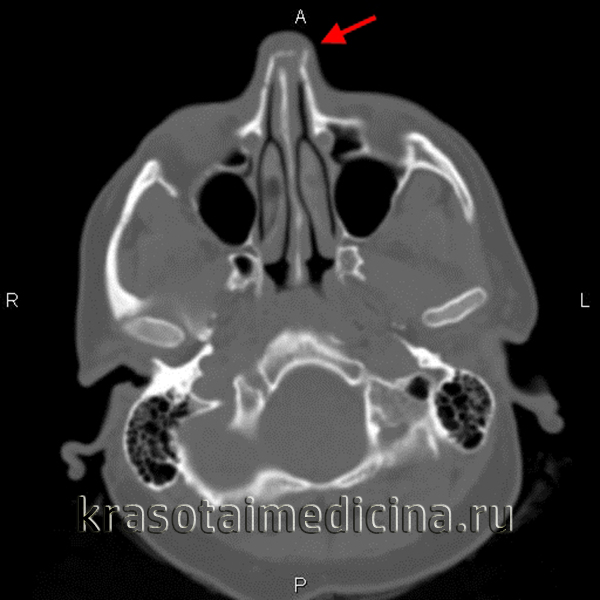

КТ голови. Перелом кісток носа зі зміщенням уламків вліво

Діагностика патології ґрунтується на даних огляду і опитування хворого, клінічних симптомах. Лікар встановлює причину травми, з’ясовує тривалість носової кровотечі, збирає анамнез життя, оглядає пацієнта, пальпує ніс, направляє хворого на рентгенографічне або ендоскопічне дослідження.

- Найбільш інформативними діагностичними методами є рентгенографічний і томографический. Оглядова рентгенограма дозволяє визначити вид перелому і поставити остаточний діагноз.